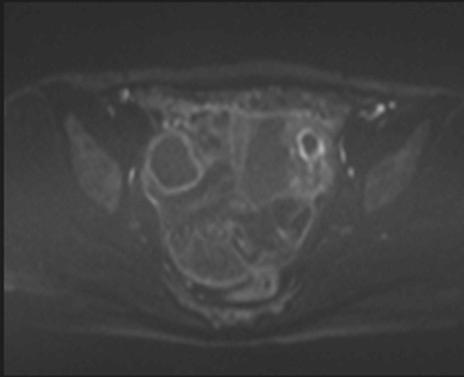

MRI(4日後)